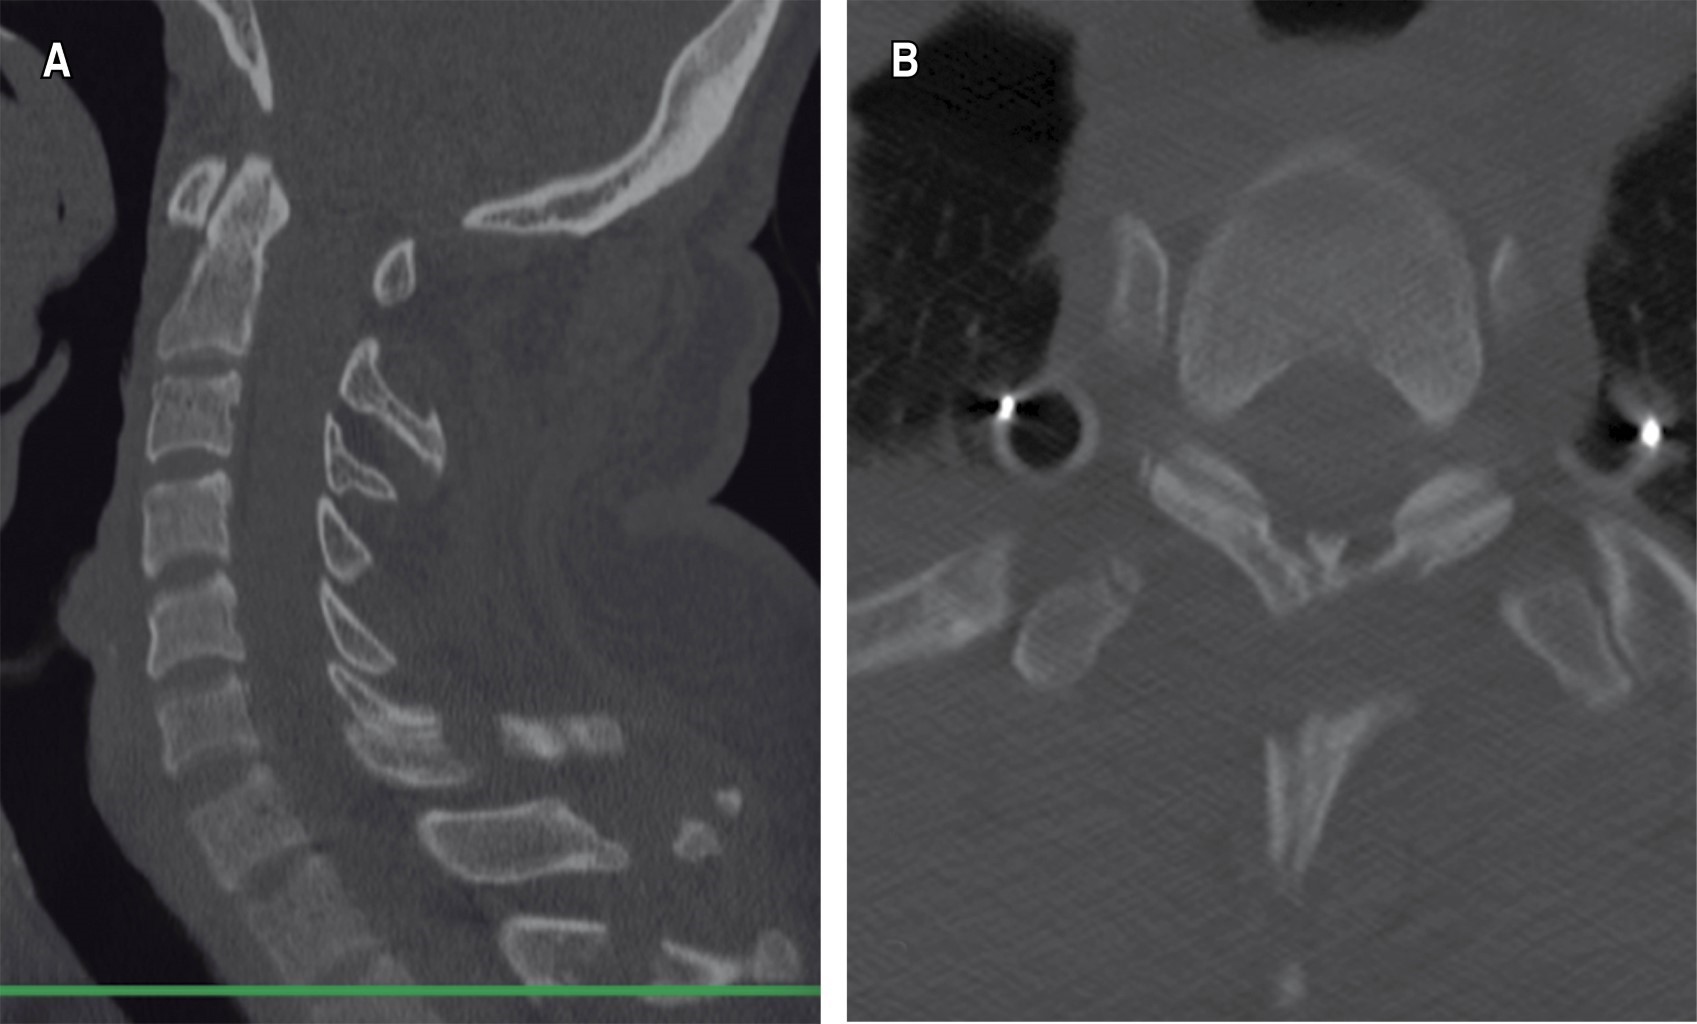

Figure 1